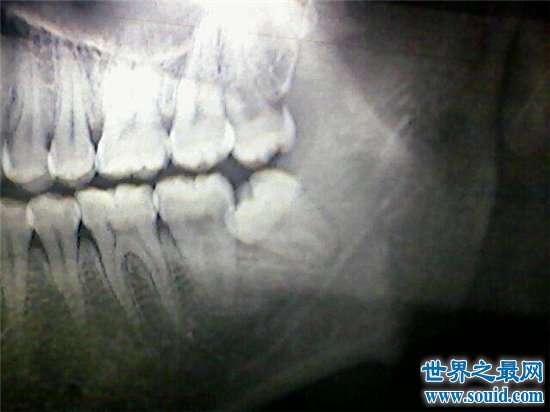

孩子是20颗牙齿,也就是说乳牙是20颗,而成年人是32颗。但是中国人有很多是没有最后四颗的,而这四颗是成年后长大的,也叫智齿。有的人不能长出,所以成年人的牙齿可以从28到32颗,但如果你拍摄X光片,你就可以看到它们。正常成年人只要没有被移除就会有32颗牙齿。

阻生牙是经常遇见的情况,特别是智齿很容易出现阻生牙的情况,阻生牙会导致邻牙的牙根吸收、邻牙蛀牙、邻牙牙周炎、牙列拥挤和冠周炎等,给口腔的健康造成极为不利的影响,因此需要尽早进行拔除。